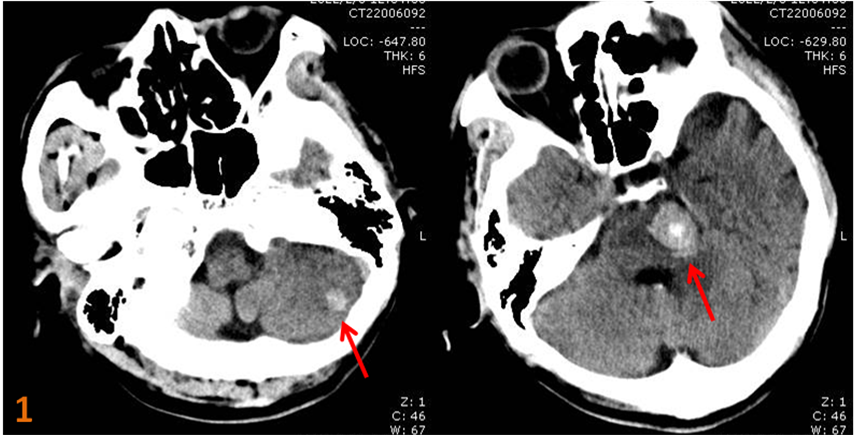

顱腦CT檢查示:“腦干、左側小腦半球類圓形高密度影,瘤卒中?腦出血?”(圖1)。

圖1.左側小腦半球、腦干高密度占位性病變。